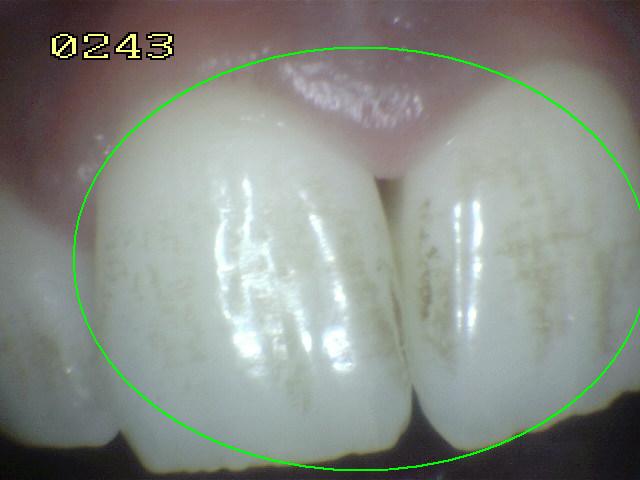

Código 2

Código 1